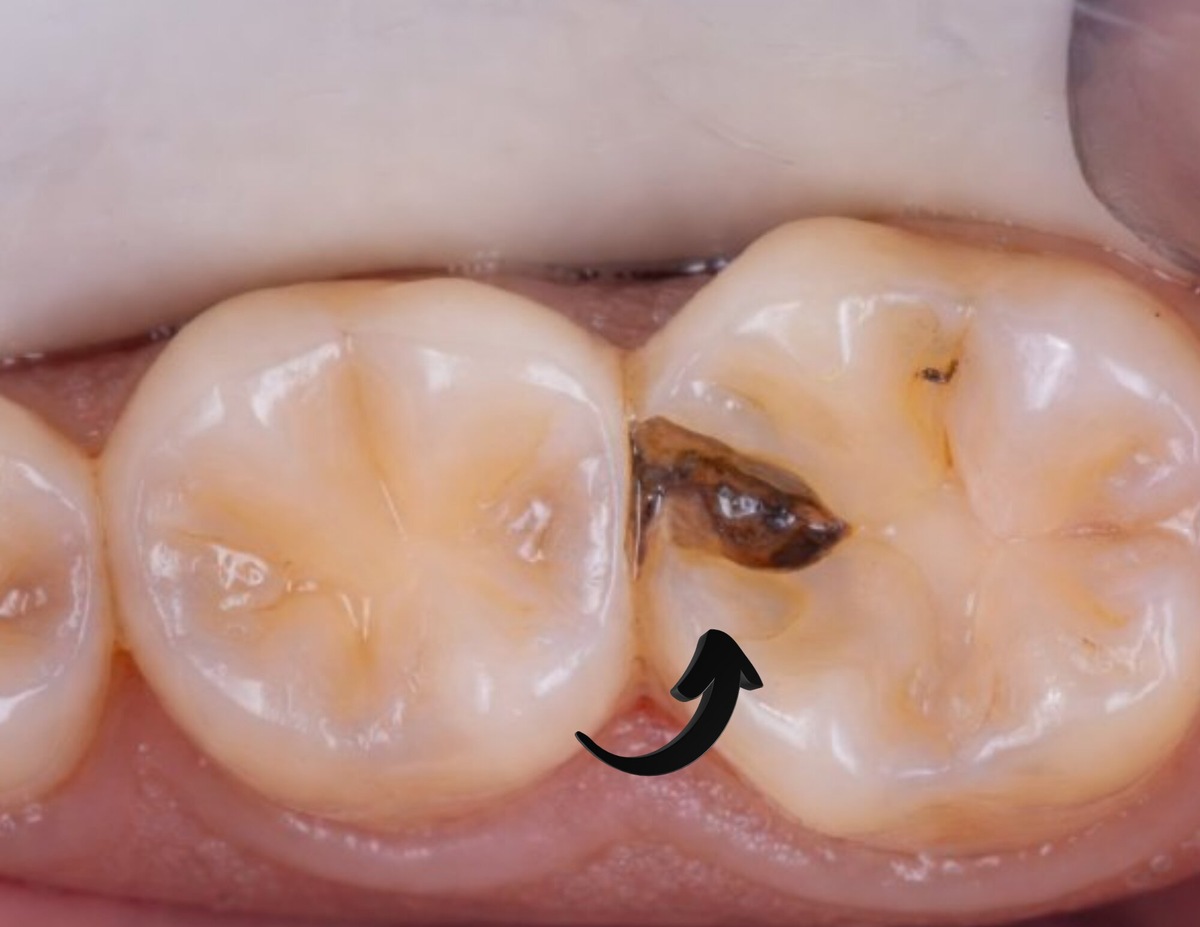

На снимке всё спокойно, боли нет, внешне зубы выглядят здоровыми. И всё же при внимательном осмотре врач обнаруживает кариес между передними зубами.

Контактный кариес появляется на тех поверхностях, которые плотно соприкасаются друг с другом. Щётка туда не проникает, а на обычном прицельном снимке эти участки частично перекрываются. Поэтому проблему нередко находят уже тогда, когда поражение дошло до дентина.

Почему стандартный снимок не всегда показывает проблему

Прицельный рентген делает изображение под таким углом, что контактные поверхности накладываются друг на друга. Небольшие очаги деминерализации могут просто «теряться» на снимке.

Чтобы увидеть межзубные зоны, выполняют прикусные снимки. Дополнительно используют трансиллюминацию — зуб просвечивают специальным светом, и участки ослабленной эмали становятся заметнее.